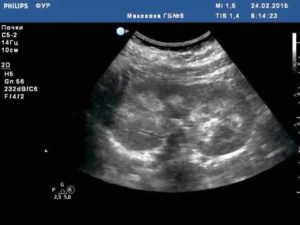

Диагностика гиперэхогенности

На экране аппарата УЗИ патологические включения имеют вид светлых или почти белых точек, отражающие ультразвуковые волны. Они могут свидетельствовать о различных заболеваниях, диагностирование которых является задачей лечащего врача.

Для диагностики гиперэхогенных изменений применяется ультразвуковое сканирование. Термином «гиперэхогенное включение» обозначается, что обнаруженные элементы имеют более яркую структуру по сравнению с собственной тканью паренхимы.